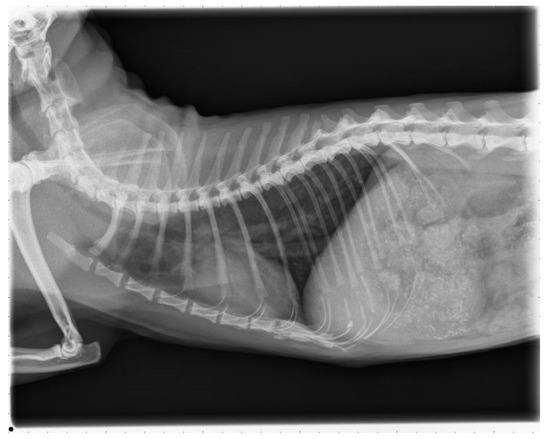

2.6. Follow Up

The cat was presented 16 months after surgery for a control examination including thoracic radiographs and echocardiography at the Veterinary Hospital in Parndorf, Burgenland. The owner reported that the cat was not showing any clinical signs despite of infrequent, spontaneous coughing and receiving the prescribed medication daily. Clinical examination remained unremarkable. The thoracic radiographs showed a moderate bronchointerstitial lung pattern without enlarged pulmonary arteries (Figure 7). This bronchointerstitial lung pattern could be due to heartworm associated respiratory disease (HARD).

Figure 7. Thoracic radiograph, right laterolateral view.